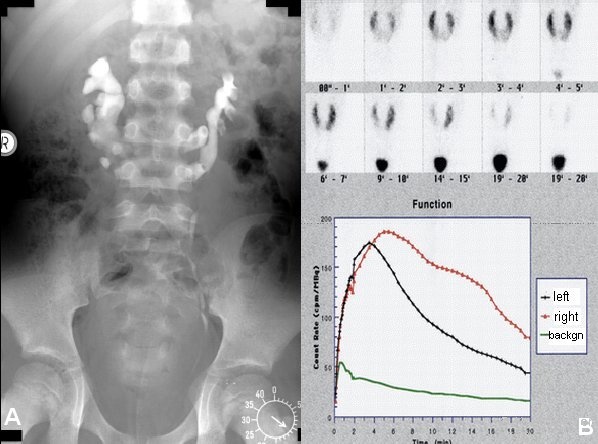

s. Männlicher Genitaltrakt/Hoden/Maldeszensus testis). Hier fanden sich beidseits malrotierte Nieren. Bei genauerer Sichtung konnte eine Gewebebrücke zwischen den unteren Nierenpolen gesehen werden - Hufeisenniere. Im i.v.-Pyelogramm ergab sich der Verdacht auf eine geringradige Abflussbehinderung des linken Anteils. Was sich auch im Isotopennephrogramm dokumentierte (Abbildung 3).

Eine operative Therapie war wegen der geringfügigen Veränderungen nicht indiziert, jedoch eine regelmäßige Kontrolle der Abflussverhältnisse aus dem oberen Harntrakt.